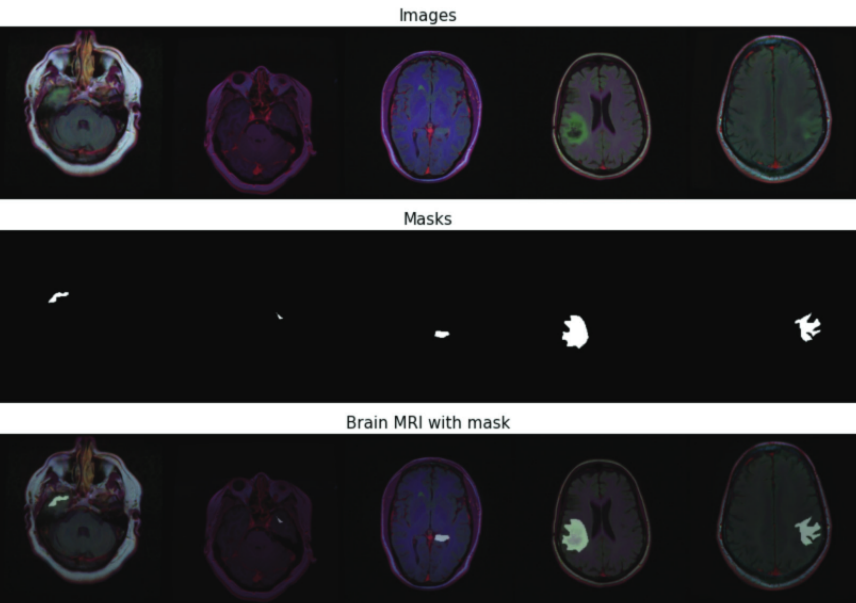

Brain MRI segmentation using segmentation models from segmentation-models-pytorch (FPN, U-Net, LinkNet, Unet++)

Brain MRI segmentation using segmentation models